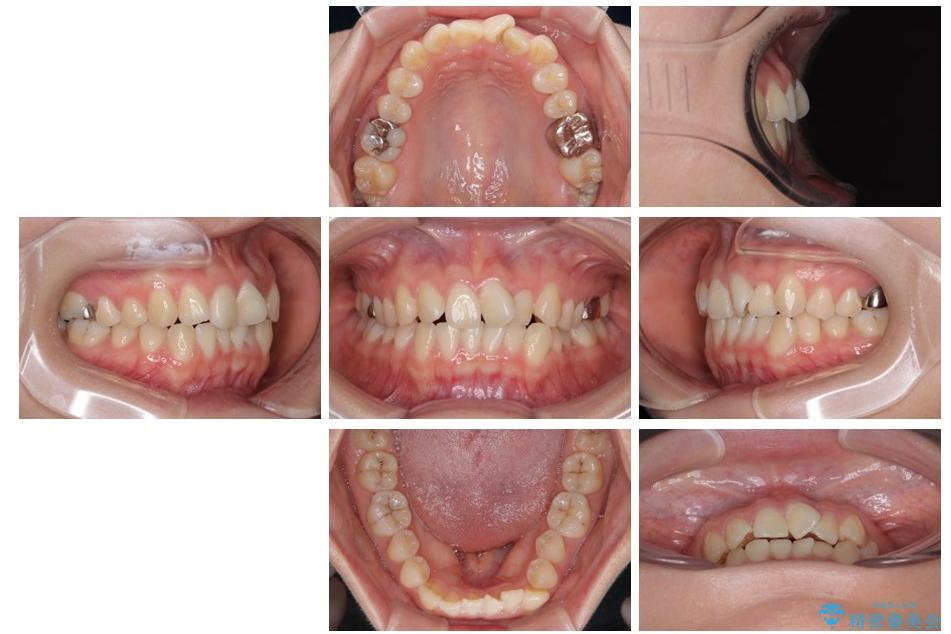

治療前

• 前歯のねじれ・ガタガタを10か月で改善!20代女性の矯正治療|クリアブラケットでむし歯になりにくい歯並びへ改善 治療前画像

治療後

• 前歯のねじれ・ガタガタを10か月で改善!20代女性の矯正治療|クリアブラケットでむし歯になりにくい歯並びへ改善 治療後画像

診察の結果、上下の前歯部に**叢生(そうせい/歯のガタガタ・重なり)**が認められました。

特に上の前歯にはねじれや重なりがあり、審美的にも清掃性にも影響している状態でした。

矯正治療期間はわずか10か月と、比較的短期間で終了しました。

前歯のデコボコがなくなり、見た目の印象が大きく変わっただけでなく、歯磨きがしやすくなり、むし歯や歯周病のリスクが大きく減少しました。